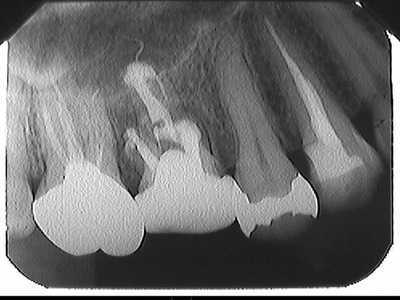

スライドギャラリー